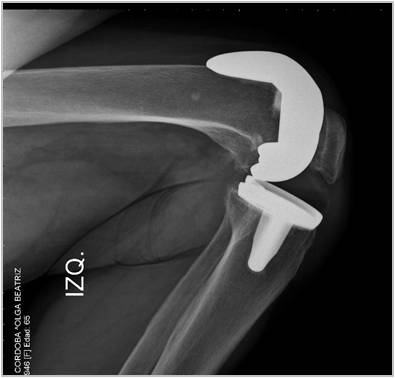

Introducción: El objetivo de este trabajo fue analizar los resultados funcionales y el rango de movimiento entre tres grupos de pacientes con artroplastia total de rodilla: dos utilizando prótesis de alta flexión y el otro con un diseño convencional. Materiales y Métodos: 64 pacientes fueron operados con prótesis total de rodilla Zimmer NexGen®, y 34 pacientes operados con Optetrack ® de alta flexión. Luego de la exclusión de pacientes; 22 pacientes (grupo A) fueron tratados con diseño de alta flexión de Zimmer, 21 pacientes (grupo B) tratados con prótesis Zimmer convencional, y 25 pacientes (Grupo C) con artroplastia Optetrack® PS. La evaluación funcional se realizó con el Knee Society Score, el Western Ontario and McMaster Universities osteoathritis index y la escala analógica visual. Resultados: En el posoperatorio, el promedio de flexión máxima del grupo A subió de 99° a 113º, con un aumento promedio de 14º, en el grupo B de 106° a 118º con una ganancia promedio de 12º y en el grupo C de 110° a 111° siendo la ganancia de 1°. Los resultados funcionales evaluados con KSS y el WOMAC presentaron mejorías en los tres grupos. Conclusión: Las evaluaciones clínicas funcionales son favorables en los tres diseños evaluados. Este estudio muestra que no hay diferencias significativas en la flexión final lograda, y resultados funcionales entre los dos primeros diseños entre sí, si siendo estos significativamente superiores al diseño del tercer grupo luego de un año de seguimiento. Palabras Claves: Prótesis total de rodilla, prótesis de alta flexión, prótesis convencionales, rango de movilidadDescargas